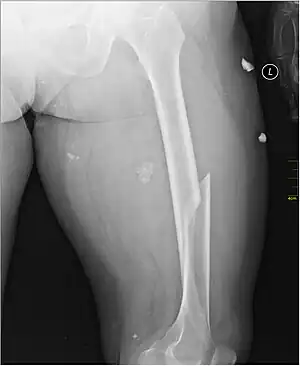

| X-ray image of a femoral shaft fracture | |

A femoral fracture is a bone fracture that involves the femur.[1] They are typically sustained in high-impact trauma, such as car crashes, due to the large amount of force needed to break the bone. Fractures of the diaphysis, or middle of the femur, are managed differently from those at the head, neck, and trochanter

Anterior-posterior (AP) and lateral radiographs are typically obtained.[4]

In order to rule out other injuries, hip, pelvis, and knee radiographs are also obtained.[5]

The hip radiograph is of particular importance, because femoral neck fractures can lead to osteonecrosis of the femoral head.[4]